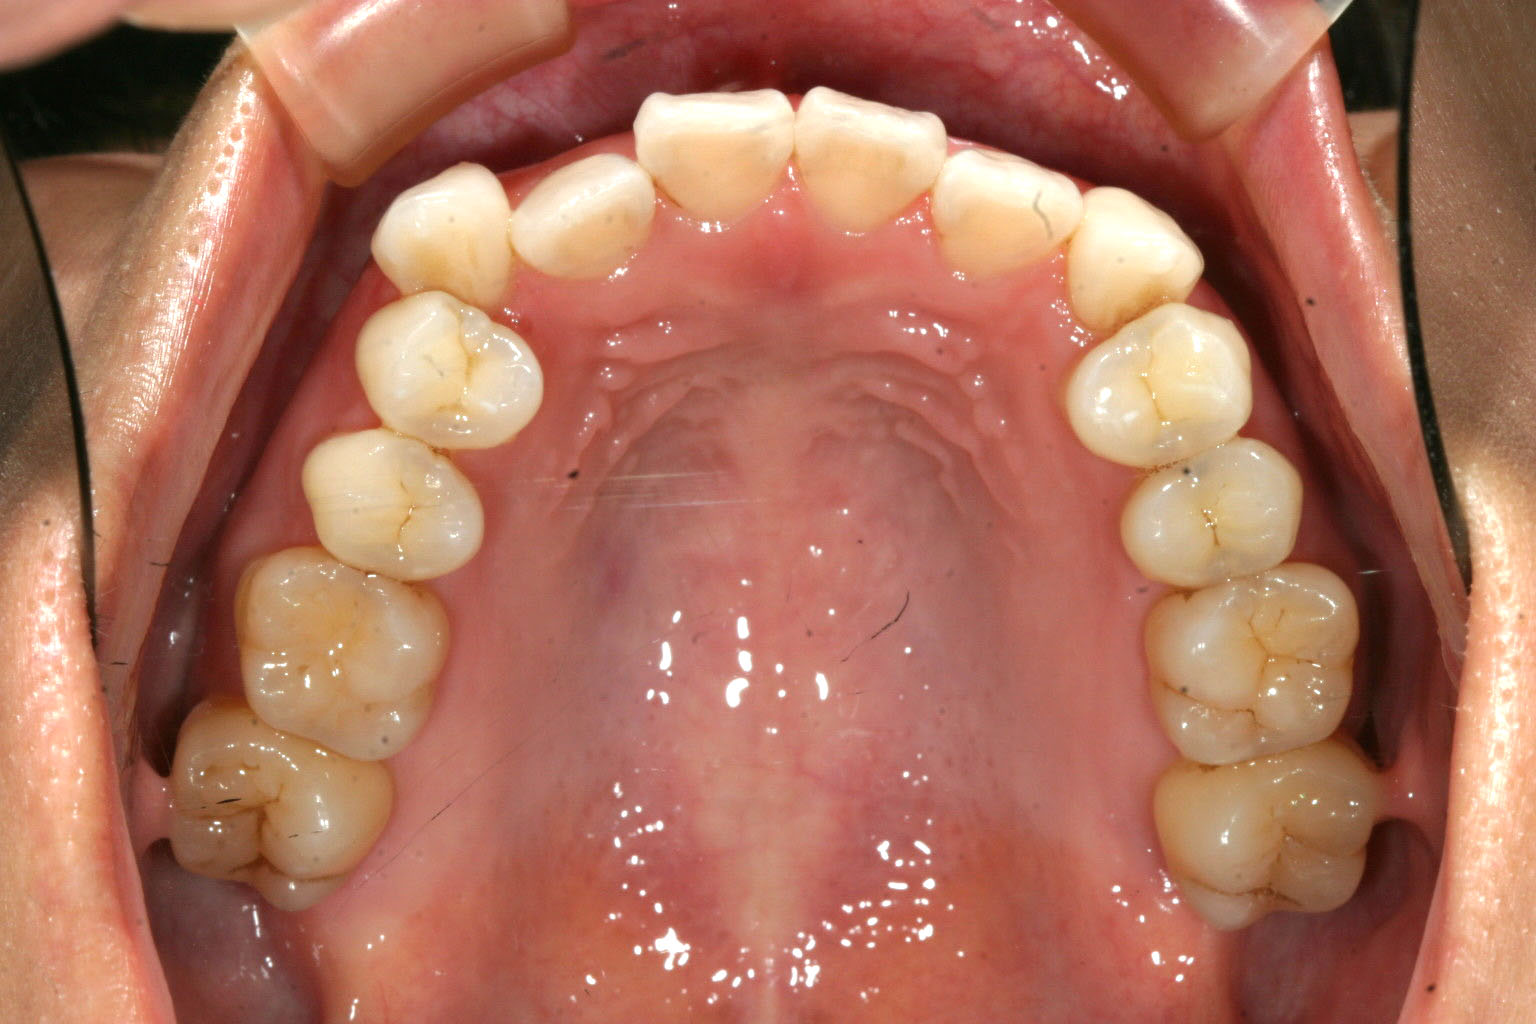

下顎のアーチが狭い為に叢生が目立ちます。

下顎のアーチも広げ叢生も改善しています。